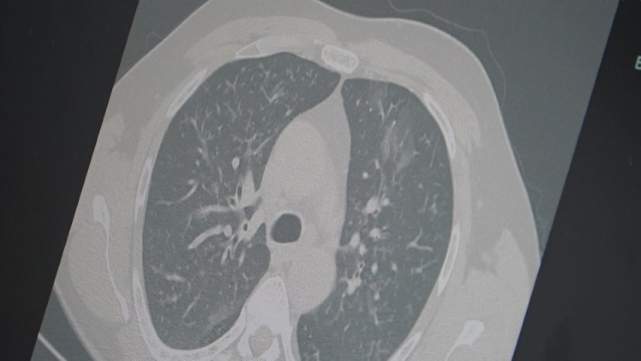

Prof. Dr. Özkaya, son dönemdeki hava şartlarına dikkat çekerek, "Sonbahar ve yaz karışımı bir iklimin etkisiyle gün içinde ani sıcaklık değişimleri yaşanıyor. Aynı gün içerisinde dört mevsimi birden yaşıyoruz. Bu durum bağışıklık sistemini zayıflatıyor ve grip benzeri şikayetlerle başlayan hastalık tabloları, üç farklı virüsün etkisiyle uzamış bir hal alıyor" dedi."Frankenstein varyantı Türkiye’de görüldü"Kovid-19’un "Frankenstein varyantı" olarak adlandırılan yeni türünün Türkiye’de de görüldüğünü ifade eden Prof. Dr. Özkaya, "Mevcut hastalarımız içinde kritik veya hayatı tehdit eden bir tablo yok. Ancak bu varyantın bulaşıcılığının yüksek olduğunu ve Avrupa ile Asya’da hızlı bir şekilde yayıldığını biliyoruz" diye konuştu."Zatürre riskine dikkat"Dr. Özkaya, grip ve kovid 19’un zatürreye dönüşme riski taşıdığını vurgulayarak, "Grip veya kovid sonrası birçok hastamızda hastalık akciğerlere iniyor ve zatürre olarak karşımıza çıkıyor. Hastaneye yatan hasta sayısında da artış gözlemliyoruz" şeklinde konuştu.

"Ayakta geçirilen ama bulaştırıcı bir salgın"Salgının günlük hayatı aksatmadan ancak sinsi bir şekilde yayıldığını belirten Özkaya, "Grip ve kovid artık yatağa düşürecek kadar ağır seyretmese de günlük işlerimizi yapmayı zorlaştırıyor. Ne tam hasta ne de tam iyilik hali olmadan virüs toplumda dolaşmaya devam ediyor. Dinlenmeyen ve izolasyon uygulamayan vakalar bulaş zincirini sürdürüyor" ifadelerini kullandı.Vatandaşlara uyarı!Prof. Dr. Özkaya, vatandaşlara şu önerilerde bulundu:"En ufak grip benzeri şikayeti olan vatandaşlarımızın evlerinde dinlenmelerini öneriyoruz. Uzamış öksürük ve nefes darlığı yaşayanların ise mutlaka doktora başvurarak akciğer röntgeni çektirmeleri ve uygun tedaviyi almaları gerekiyor."